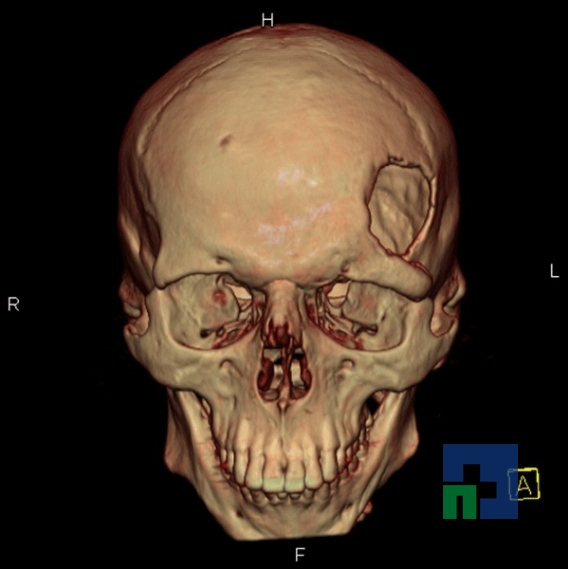

- Diagnosticul fracturilor:

-

- Unice

- Multiple

- Cu înfundare

- Complexe cranio-sinusale

- Complexe cranio-etmoidale

- Complexe cranio-orbitare

- Complexe cranio-faciale